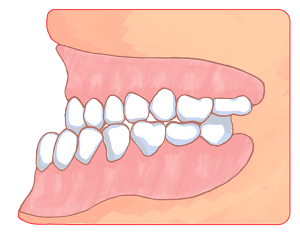

「いびき」と「口輪筋」の関係

「いびき」と「口輪筋」の関係